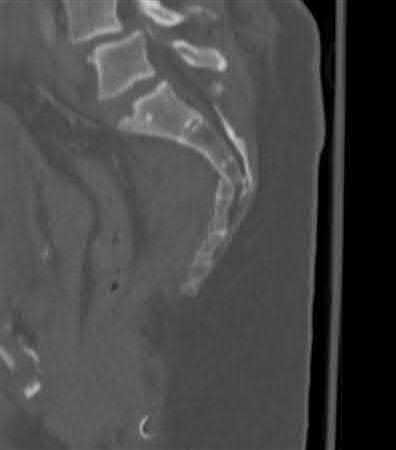

The clinical presentation is consistent with a chronic sternoclavicular dislocation, which is defined as being greater than 3 weeks old. The 3D CT image shows posterior displacement of the medial clavicle relative to the sternum. Chronic anterior dislocations are recommended to be treated conservatively, especially if not symptomatic, but as this is a posterior dislocations, current recommendations are to treat them with reduction in order to avoid delayed issues with the medial clavicle interacting with the mediastinal structures.